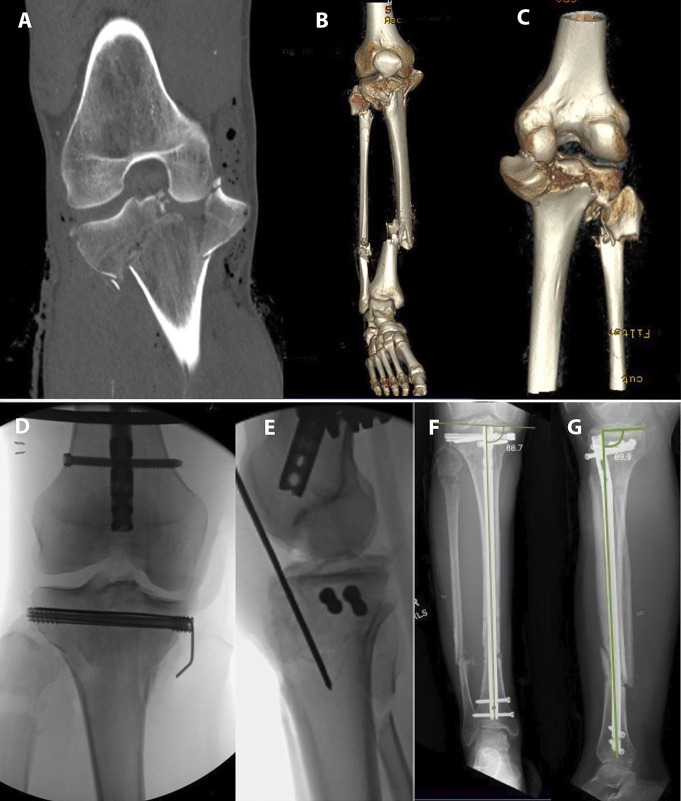

目的:比较髌上髓内钉(IMN)与双钢板切开复位内固定(ORIF)治疗双髁胫骨平台骨折(OTA/ ao41 - c2 /C3)的关节复位和对准维持效果。设计:回顾性队列研究。环境:单一一级学术创伤中心。患者/参与者:2012年7月至2022年7月期间接受治疗的58名成年人(28名IMN, 30名ORIF);各组根据年龄、体重指数和骨折类型进行匹配。干预措施:与标准开放入路行双钢板ORIF相比,采用≥1枚独立拉力螺钉的半扩展髌上IMN。主要结果测量:关节线凹陷、髁突加宽、胫骨内侧近端角(MPTA)和胫骨后部近端角(PPTA)愈合(12个月)。结果:ORIF队列的初始位移更大(关节线8.2 mm vs 5.6 mm, P = 0.014;扩大7.2 mm vs 5.8 mm, P = 0.150)。在12个月时,愈合的宽度(0.6 mm IMN vs 1.0 mm ORIF, P = 0.856),愈合的凹陷(2.0 mm vs 1.1 mm, P = 0.991), MPTA(89.9°vs 89.6°,P = 0.699)和PPTA(11.3°vs 9.8°,P = 0.078)没有差异。没有发生需要修正的二次复位损失。结论:髌上IMN维持了OTA/AO C1、C2和某些C3骨折愈合后的关节线移位、髁突加宽、MPTA和PPTA。手术恢复和维持MPTA和PPTA。该技术在胫骨平台骨折的ORIF使软组织包膜处于危险中或在其他情况下首选髓内植入物的情况下可能有用。证据等级:三级。

Objectives: Compare maintenance of articular reduction and alignment in bicondylar tibial plateau fractures (OTA/AO 41-C2/C3) treated with suprapatellar intramedullary nailing (IMN) versus dual-plate open reduction and internal fixation (ORIF).

Intervention: Semiextended suprapatellar IMN with ≥1 independent lag screw compared with dual-plate ORIF performed through standard open approaches.

Main outcome measurements: Joint-line depression, condylar widening, medial proximal tibial angle (MPTA), and posterior proximal tibial angle (PPTA) at union (12 months).

Results: Initial displacement was greater in the ORIF cohort (joint-line 8.2 mm vs. 5.6 mm, P = 0.014; widening 7.2 mm vs. 5.8 mm, P = 0.150). At 12 months, healed widening (0.6 mm IMN vs. 1.0 mm ORIF, P = 0.856), healed depression (2.0 mm vs. 1.1 mm, P = 0.991), MPTA (89.9° vs. 89.6°, P = 0.699), and PPTA (11.3° vs. 9.8°, P = 0.078) did not differ. No secondary loss of reduction requiring revision occurred.

Conclusion: Suprapatellar IMN maintained healed joint line displacement, condylar widening, MPTA, and PPTA in OTA/AO C1, C2, and certain C3 fractures. The MPTA and PPTA were surgically restored and maintained. This technique may be useful in certain circumstances where ORIF of the tibial plateau fractures places the soft tissue envelope at risk or where an intramedullary implant is otherwise preferred.